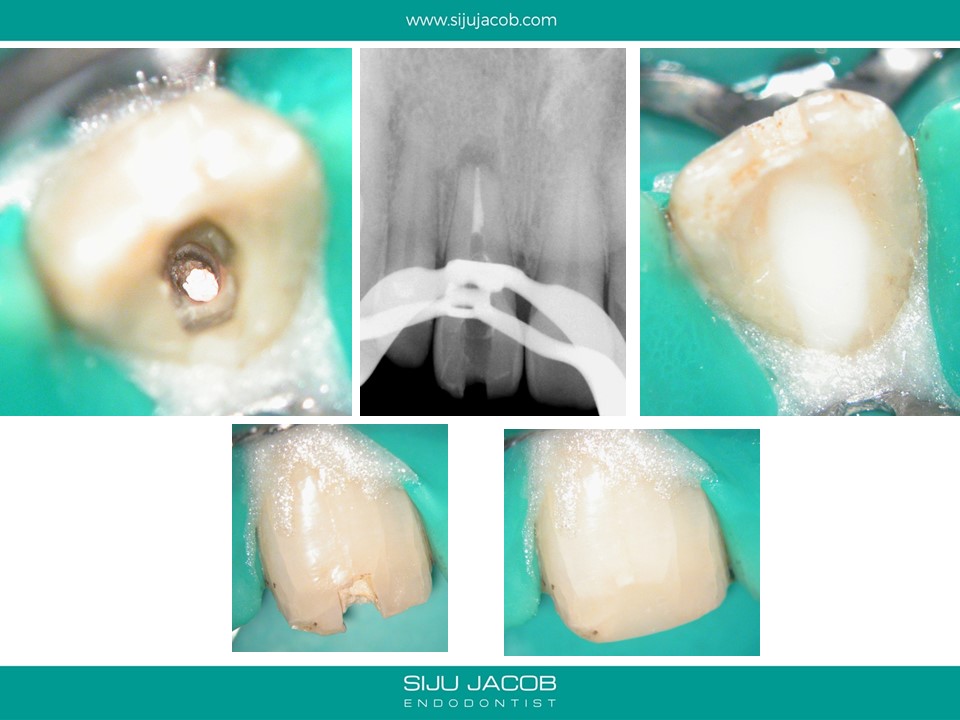

This case was referred by another practitioner who attempted to locate the canal, but couldn’t find it. The practitioner had perforated palatally in an effort to search for the canal. The perforation was supra-crestal and was sealed with Glass Ionomer. When viewed under the microscope, one can clearly see the calcified portion of what used to be the canal at one time. Once we are able to differentiate between the calcified canal and the adjacent dentine, it becomes predictable to drill apically to locate the canal.